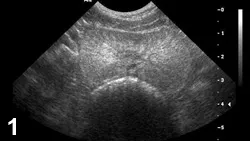

FIGURE 1

Typical ultrasonographic finding with BPH. Transverse image (ventral at top of image) of an intact canine prostate with multiple wagon-wheel striations radiating from the urethra to the capsule.

• Characteristic appearance of BPH and CBPH on ultrasonography includes symmetric parenchymal striation with increased echogenicity and variable hypoechoic-to-anechoic intraparenchymal cystic structures (Figures 1 and 2).